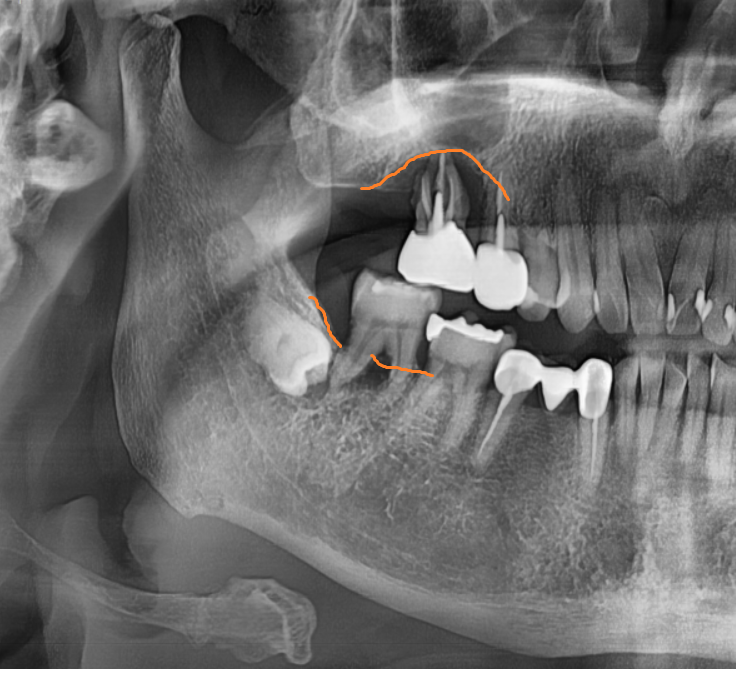

23.10.05

오른쪽 위아래 어금니 모두 문제가 있었습니다.

두번째로 오른쪽 위 어금니

육안으로 잇몸 뾰루지처럼 볼록하게

올라온게 보이시죠??

치아 뿌리 염증이 잇몸 밖으로

올라온겁니다.